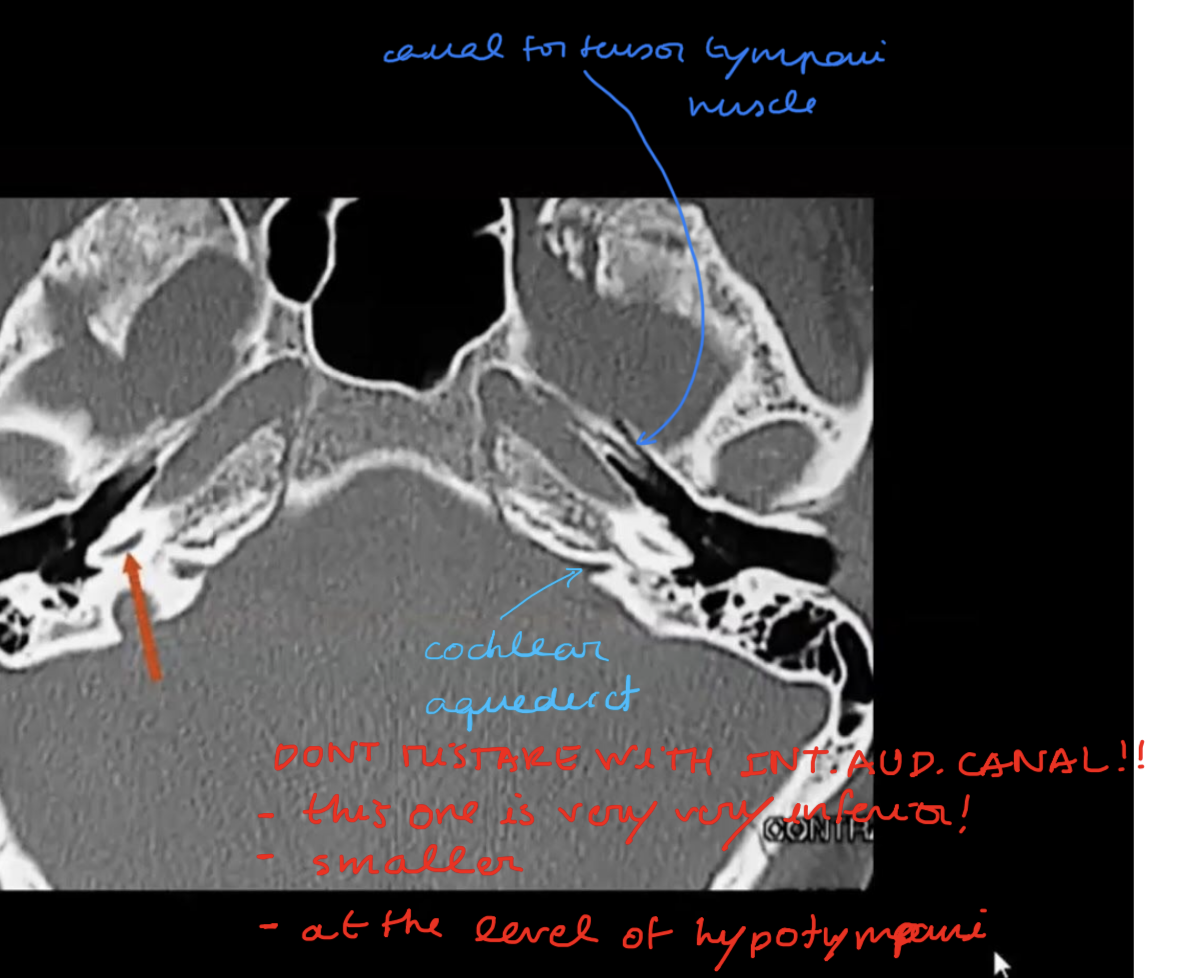

Tell the traject of the facial nerve in the skull base?

Nerves inside the IAC with subdivisions?